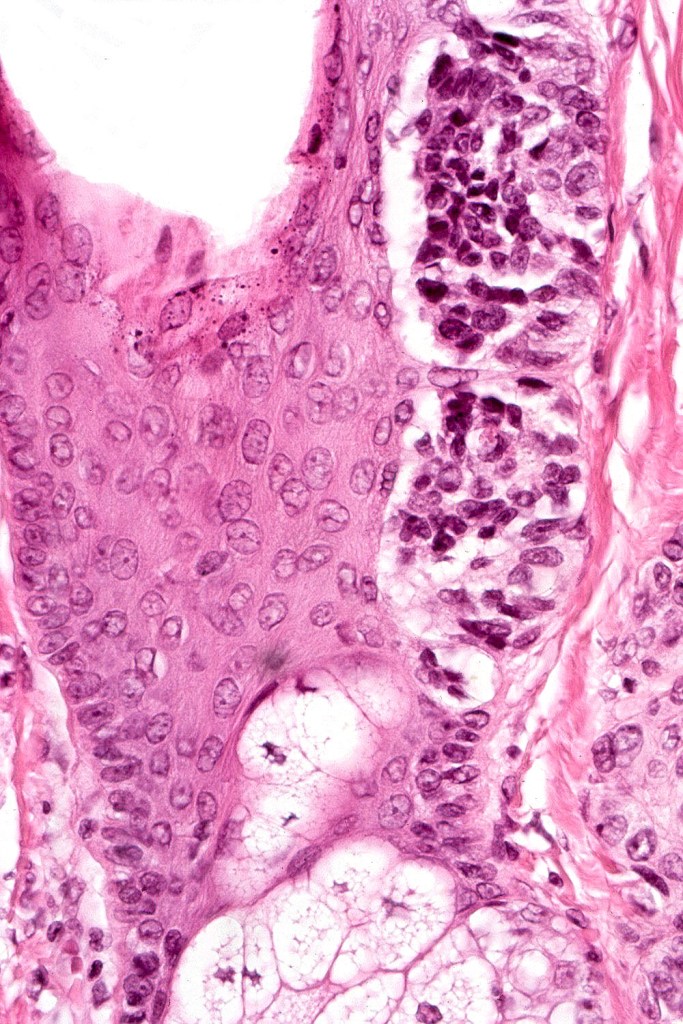

Atypical congenital nevus of the neonate

•Very exceptional finding, generally in small congenital nevi

•May also present in young children

•Characterized by large abnormally distributed junctional nests

•Pagetoid spread (can mimic superficial spreading melanoma)

•Atypical dermal component

•Junctional & dermal mitotic activity

•Impaired or absent maturation

•Involvement of the appendages

Diagnosis very much depends on clinicopathological correlation. It would be easy to make a misdiagnosis of dysplastic nevus or melanoma if the clinical information is unknown.